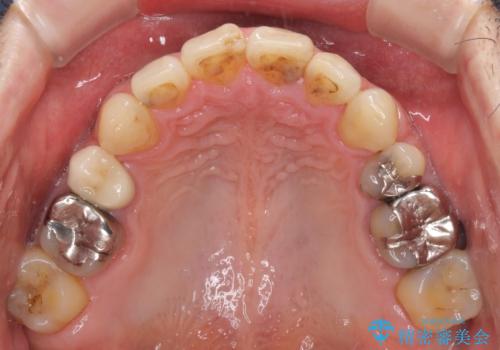

- むし歯による奥歯の痛みを気にして来院された患者様です。

神経にまでむし歯の及んでいる歯や、既に根管治療がされている歯に痛みがあったため、まずは根管治療を行うこととしました。

その後、以前行った抜歯矯正の後戻りをインビザライン・ライトにより改善し、むし歯や銀歯はオールセラミッククラウンにて補綴治療することとしました。

痛みは速やかに引き、銀歯や黒く変色したむし歯がセラミッククラウンで自然な色合いに仕上がり、患者様には大変満足していただきました。